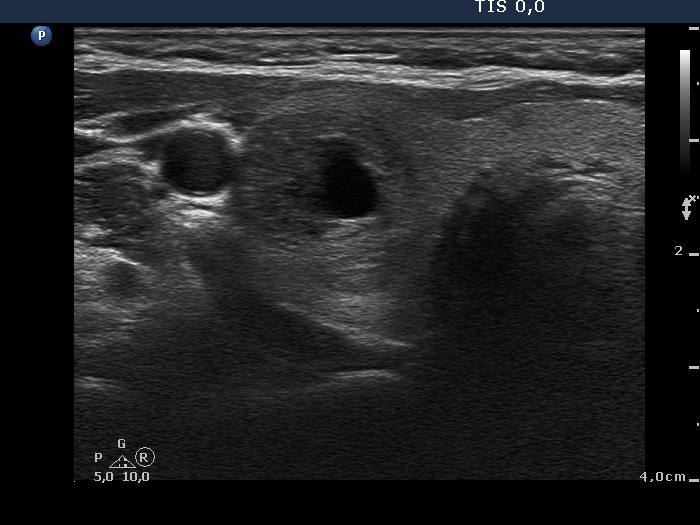

Ultrasonography. The thyroid was echonormal and contained numerous nodules with different echogenicities.

Cytology was performed from two lesions located in the right lobe and resulted in benign colloid goiter and in benign cystic-colloid goiter, nodule in the middle-dorsal part and in the lower pole, respectively.